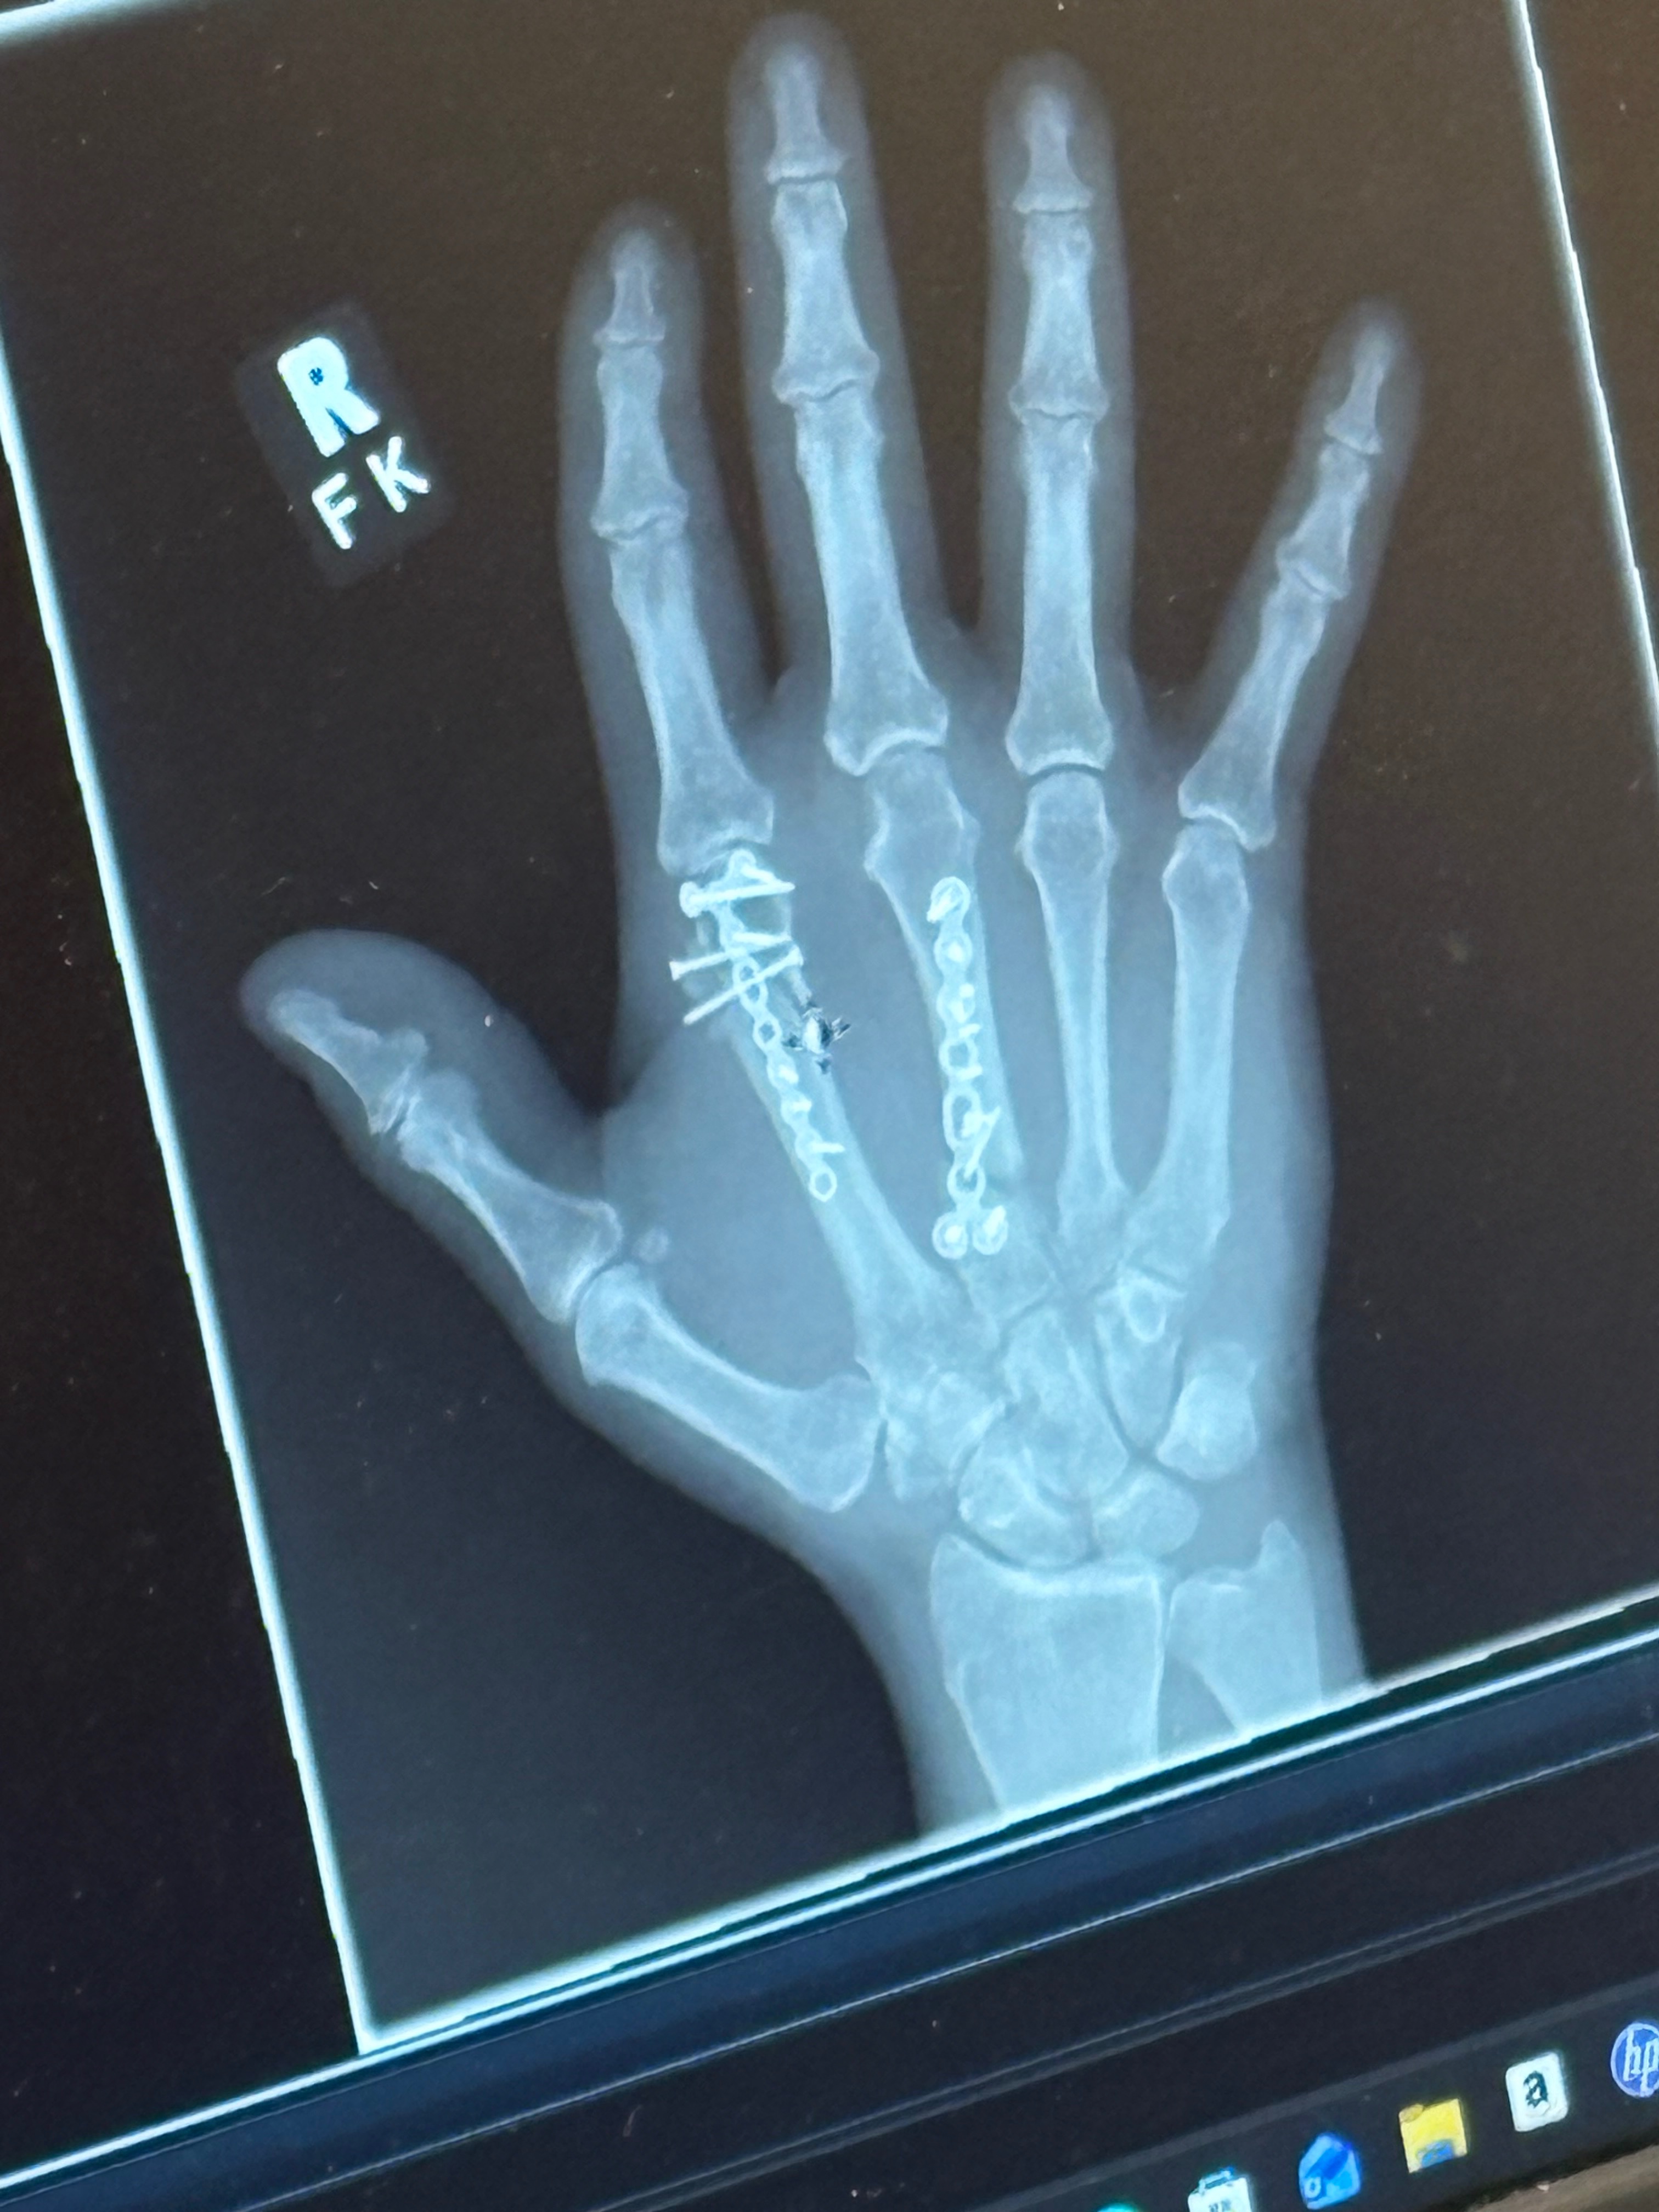

He ended up having basically an emergency surgery that night which went into the next day. He was in surgery for about 2-2 1/2 hours. He now has plates and screws in his hand. Two bones in the top of his hand were affected:

1. The bone leading up to the pointer finger were crushed in 8 places.

2. The bone leading up to the middle finger was broken in 2 places.